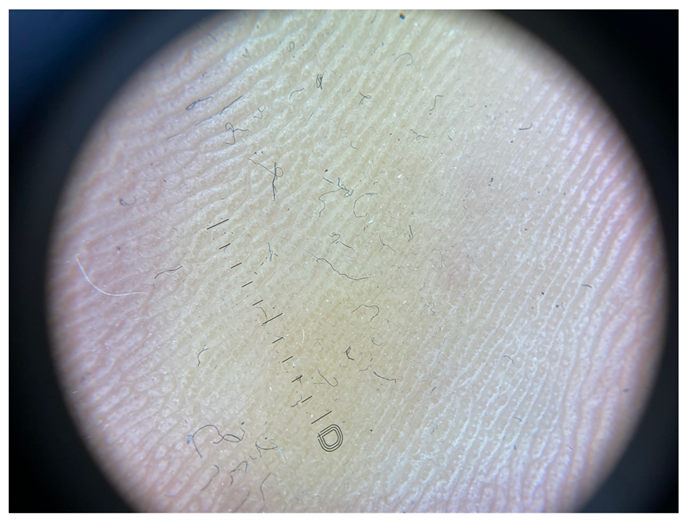

| Grade II | Foto Finder dermatoscopy, cross-polarization |

![]() | |

| DL-5 dermatoscopy, cross-polarization | |

| DL-5 dermatoscopy, parallel polarization | |